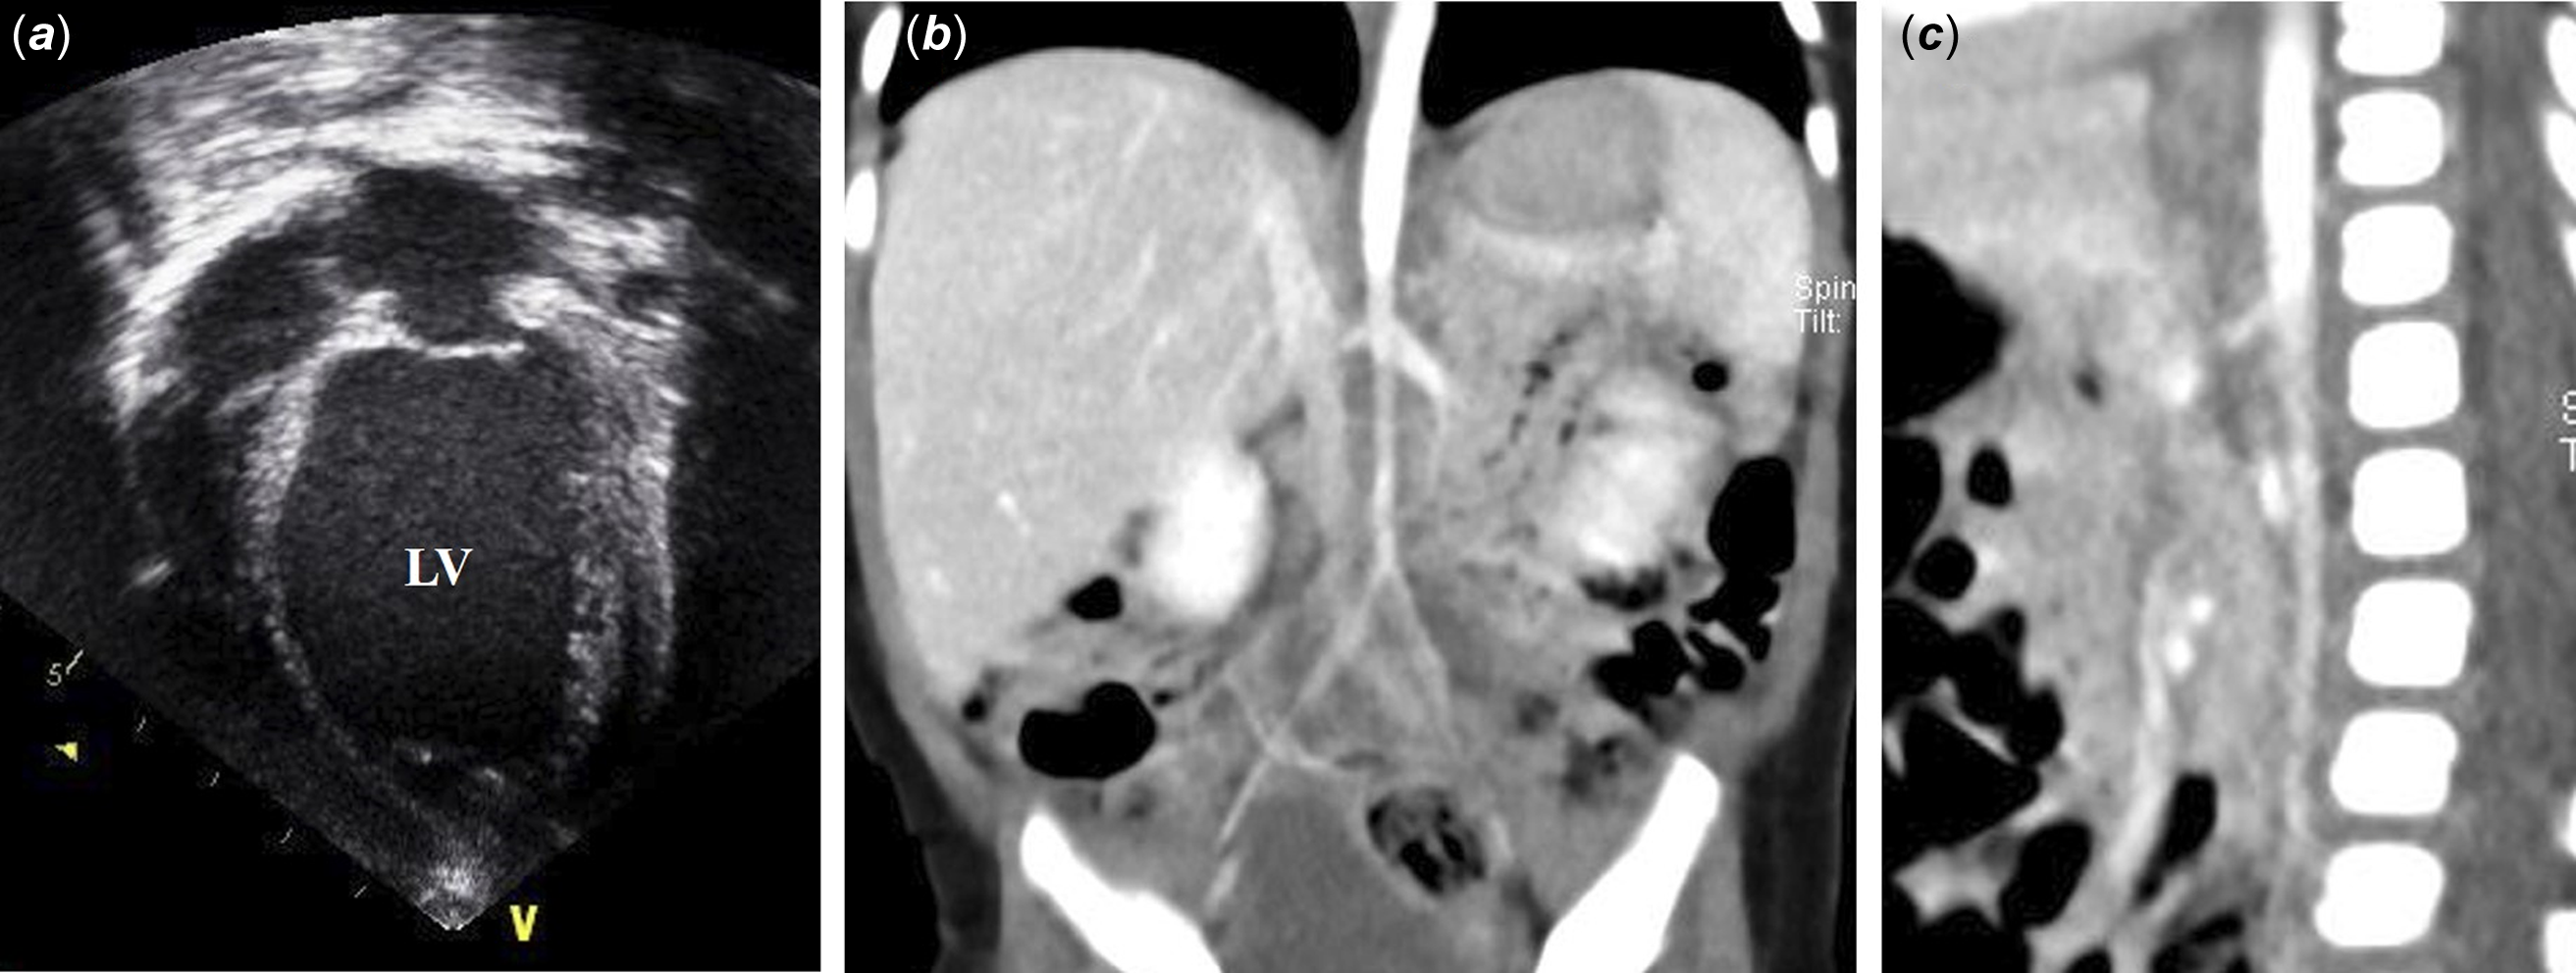

A child with spontaneous resolution of idiopathic mid-aortic syndrome presented with dilated cardiomyopathy

Mid-aortic syndrome is an uncommon vascular disease characterised by lower thoracic and upper abdominal aorta stenosis and can occur even in neonatal or infant periods. Here, we report an interesting case of a 2-month-old female with diffuse hypoplasia of the lower abdominal aorta and secondary dilated cardiomyopathy. In our patient, her abdominal aortic narrowing spontaneously normalised over time with the administration of consistent and goal-directed heart failure therapy, supporting adequate growth and natural recovery.